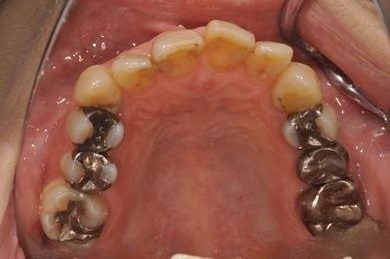

| 性別/年齢 | 女性 / 54歳 | ||||||||||||||||||||||||||||||||

| 治療内容 | インプラント1本、メタルボンドセラミック1本 | ||||||||||||||||||||||||||||||||

| 総治療費 | 445,238円 | ||||||||||||||||||||||||||||||||

| 治療期間 | 5ヶ月 |